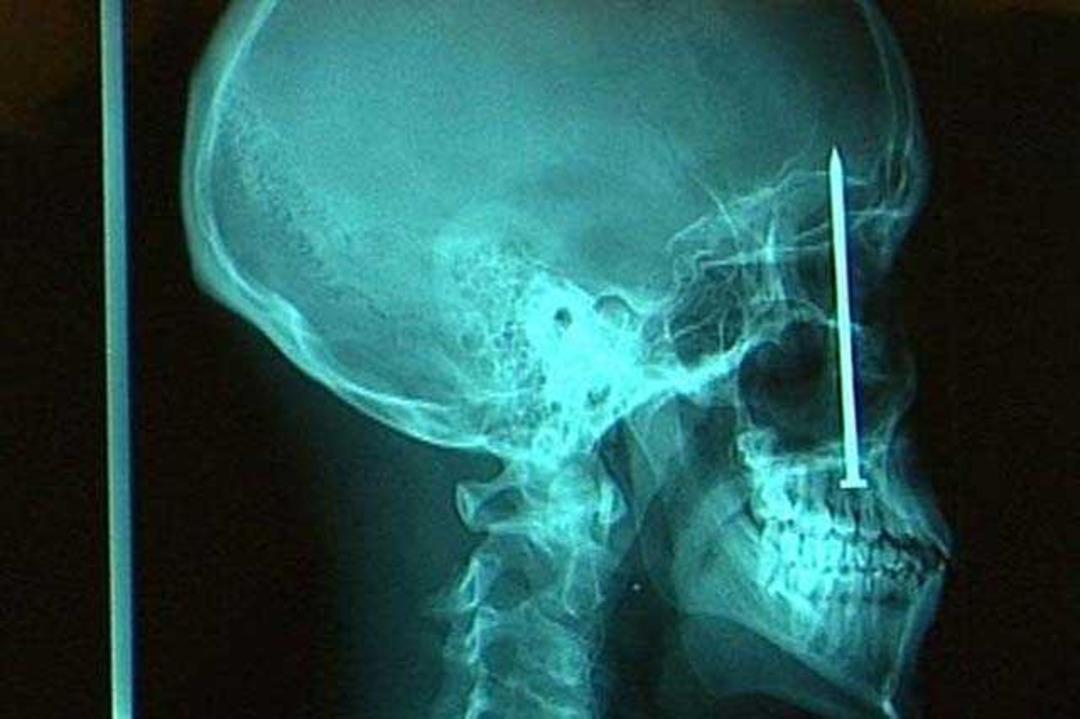

Kafatasında bir çivi bulunan adam, bir hafta önce çivi makinesi ile çalışırken bir sorun yaşamıştı. makine tepmiş, adamın ağzından içeri bir çivi göndermiş ve bu çivi kafatasına kadar gitmişti!